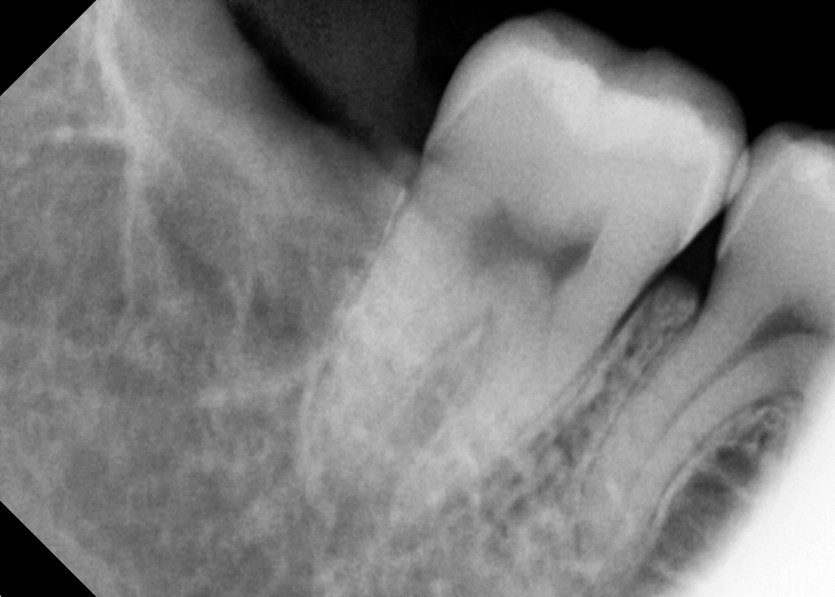

#48 사랑니 발치

구강 외과 전문의가 당일 발치했습니다.